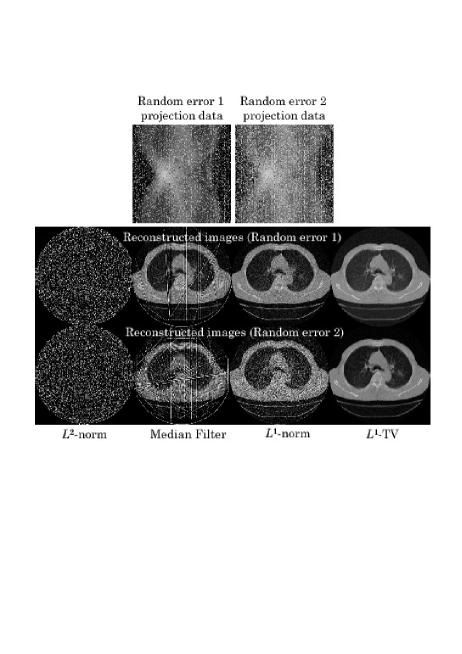

[Scenario 3](Random Errors) Two cases were simulated. In the first case, randomly selected projection data bins (20 percent) were contaminated with the abnormal errors (Random Error 1). In the second case, randomly selected projection data bins (30 percent) were contaminated with the abnormal errors (Random Error 2).

In all the scenarios, we used a single transaxial slice of chest CT scan image consisting of 320320 pixels. The simulated projection data was computed with the sampling of 320(angles)320(radial bins), from which an image consisting of 320320(pixels) was reconstructed. We have compared the following four different algorithms.

[-Norm Reconstruction] The -norm reconstruction of Eq. (22) was implemented with the iteration number 50.

[Projection Space Median Filter] This is an empirical method to remove the effect of abnormal errors. The median filter is applied to degraded projection data to remove the abnormal errors followed by the -norm reconstruction. The window size of median filter was empirically determined in such a way that visual quality of reconstructed image is best dependent on each case.

[-Norm Reconstruction] The -norm reconstruction (Algorithm 2) was implemented with the iteration number 50.

[-TV Reconstruction] The -TV reconstruction (Algorithm 3) was implemented with the iteration number 50.

We show reconstructed images together with the degraded projection data for all the scenarios in Figs. 3-5. In all the scenarios, the images by the -norm reconstruction were severely damaged by the abnormal errors, in which the artifact patterns, i.e. streaks, random errors, etc., depend on the locations of abnormal bins. The empirical projection space median filtering succeeded in reducing the artifacts, but the filtering also affects the correct data so that we can observe some additional artifacts in the final images. On the other hand, for the cases of Detector Error 1, Angle Error 1, and Random Error 1 with relatively mild errors, the power of identifying the abnormal bins in both the -norm and -TV reconstructions were significant in which they succeeded in reconstructing almost perfect images. However, the difference between the -norm reconstruction and the -TV reconstruction became apparent for the more difficult cases of Detector Error 2, Angle Error 2, and Random Error 2. In these cases, the -TV reconstruction correctly identified most of the abnormal bins whereas the -norm reconstruction did not succeed perfectly. With respect to convergence speed of the -norm and -TV reconstructions, they were a bit slower compared with the -norm reconstruction and the standard ART algorithm mainly because early iterations need to be spent to correctly identify the locations of abnormal bins. However, thanks to their row-action structures, they seem to be still significantly faster than using the standard -norm and -TV minimization algorithms (for example, popular iterative reweighted least-squares method [3],[4]) which can be used for the same cost functions.